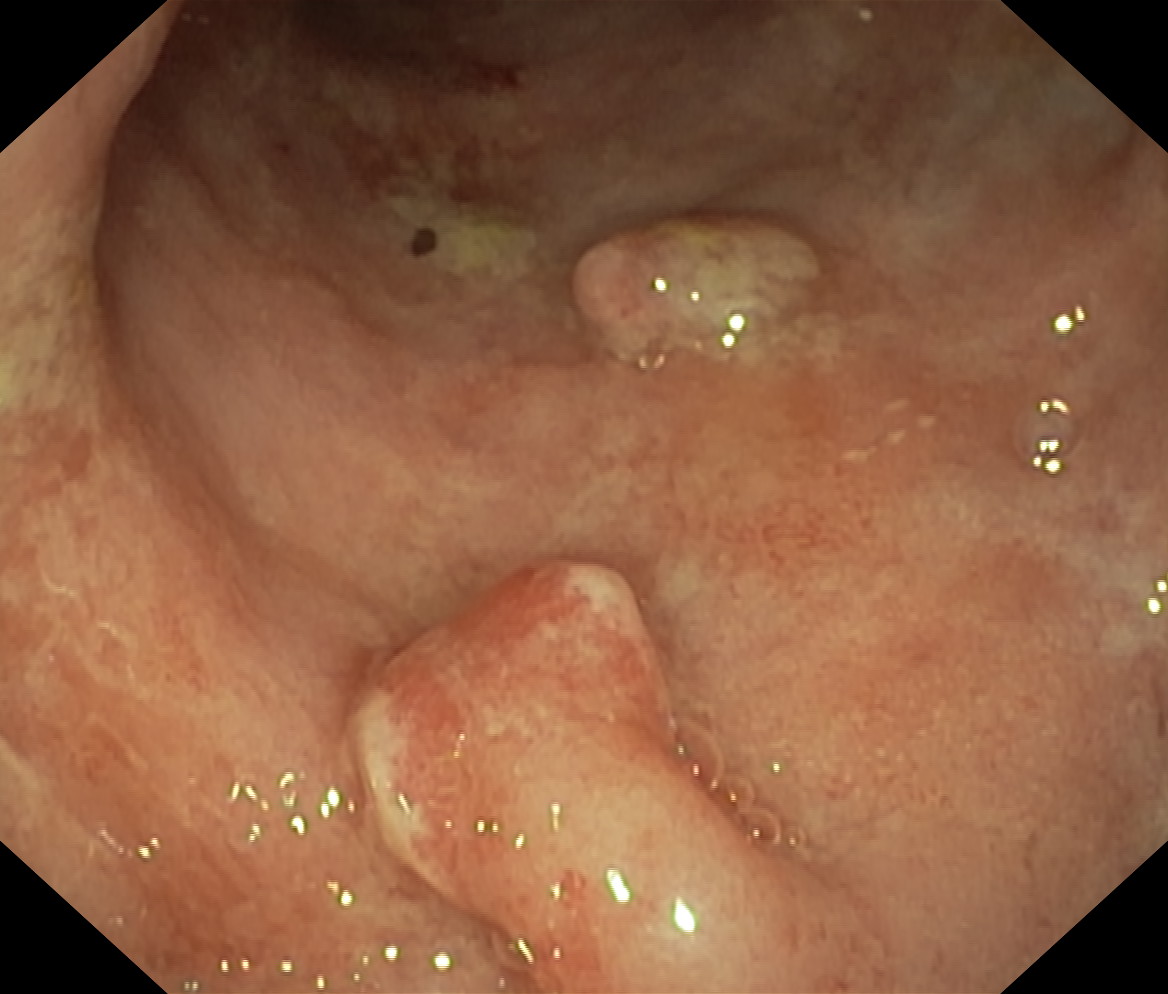

Polipy

Polipowatość